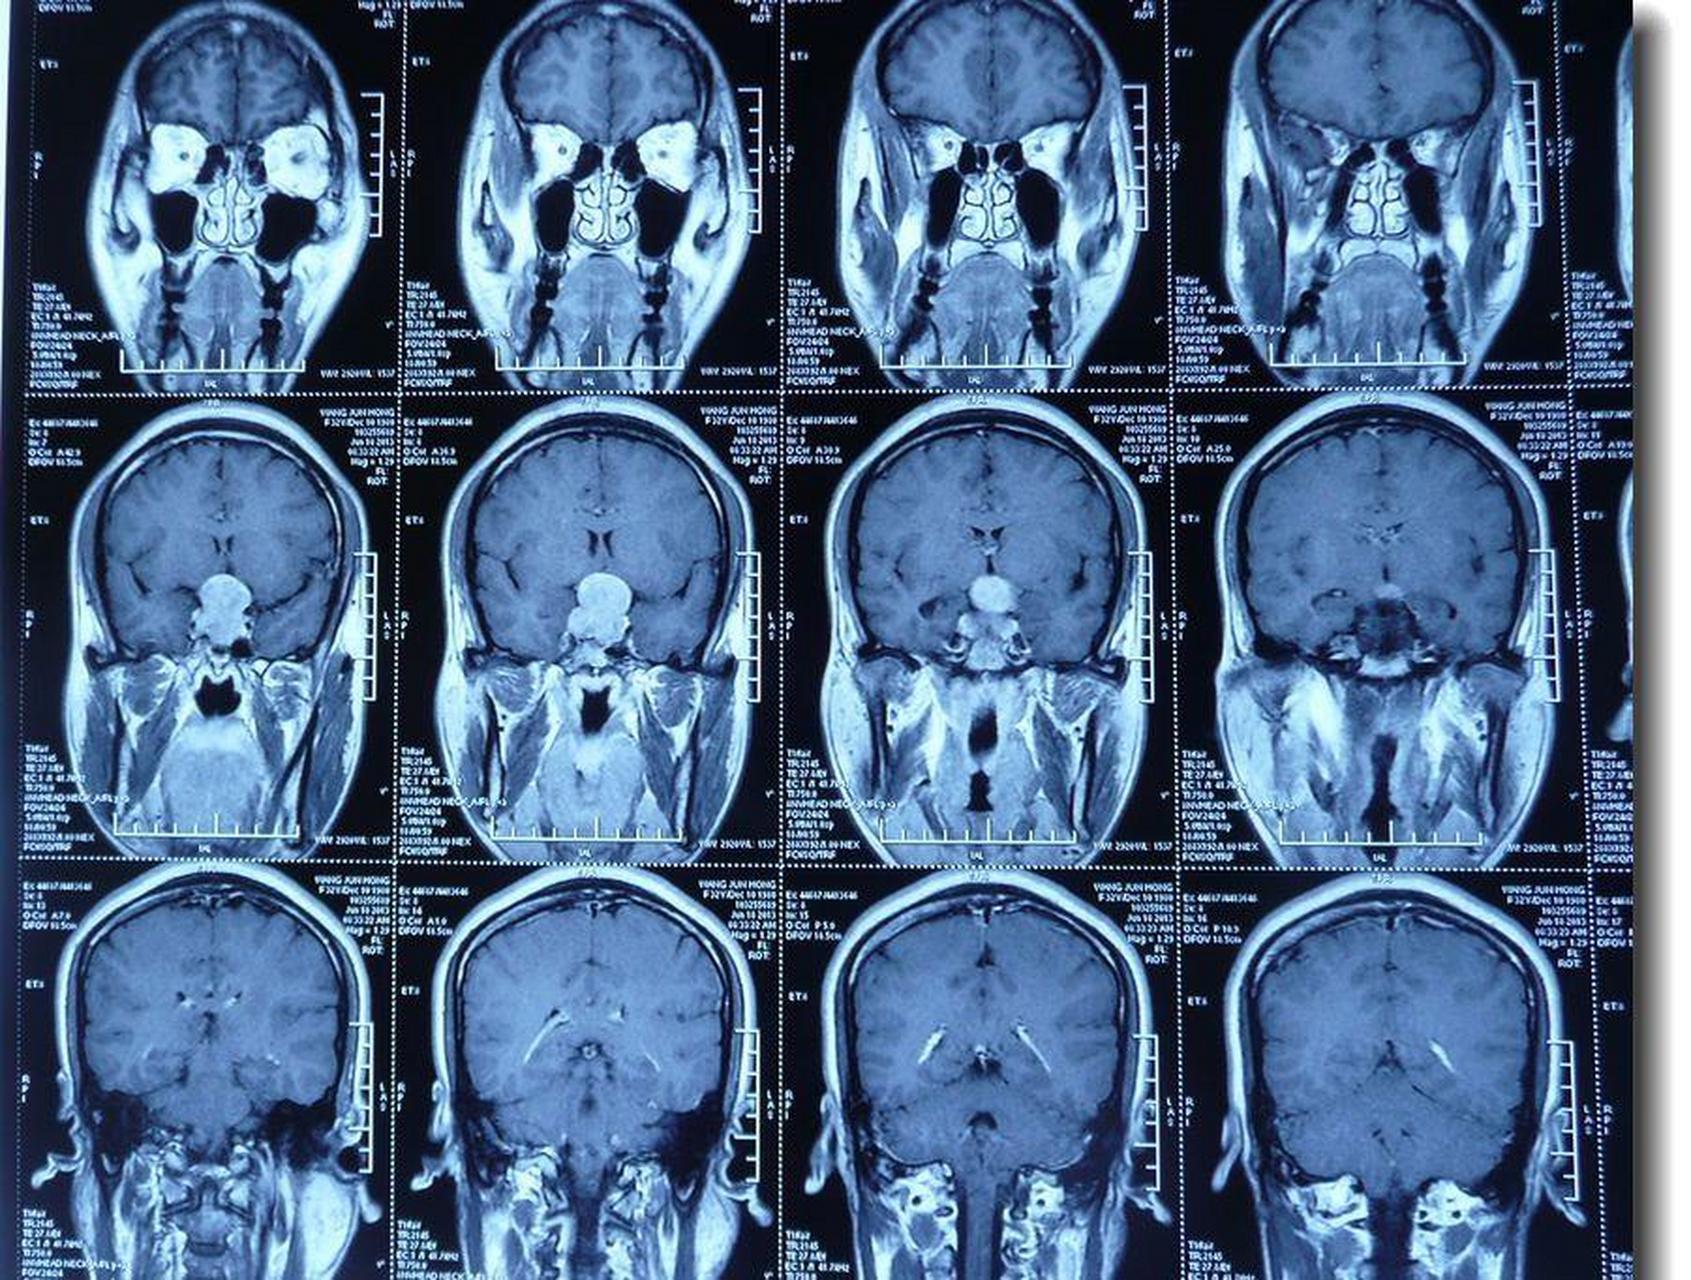

核磁确认垂体瘤

图片尺寸3021x4029